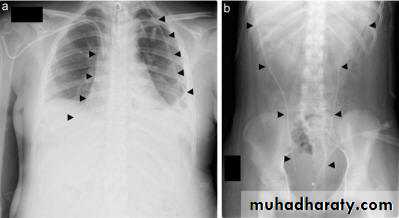

What is a surgical or subcutaneous emphysema?

Surgical emphysema

What is the difference??Surgical Emphysema